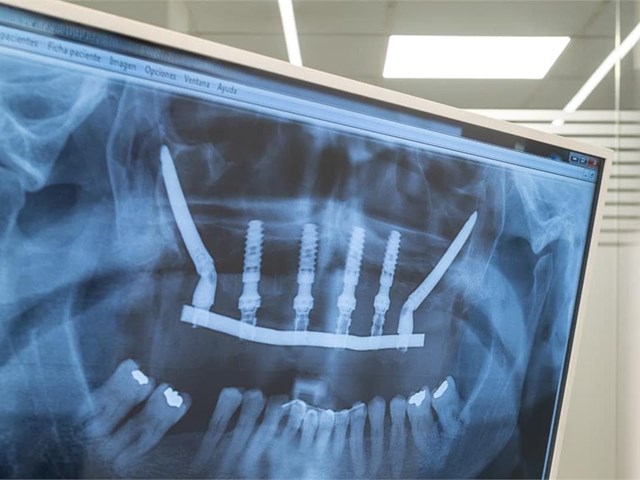

¿Es doloroso el proceso de colocación de implantes dentales? 13 oct

¿Es doloroso el proceso de colocación de implantes dentales?

13/10/2025 Implantes

Todos los procedimientos que se hacen en el sillón de un dentista tienen algo en común: el medio a que duela. Por mucho que expliquemos que existe la anestesia y la sedación para que eso no ocurra, sigue siendo el temor más habitual de los pacientes. Realmente, en el caso de algunos procedimientos concretos lo llegamos a entender. Y es que tener cierto recelo, por ejemplo, a los implantes dentales entra dentro de lo normal. ¿Es tu caso? Pues deja de darle vueltas: en Titanium Clínica Dental &...